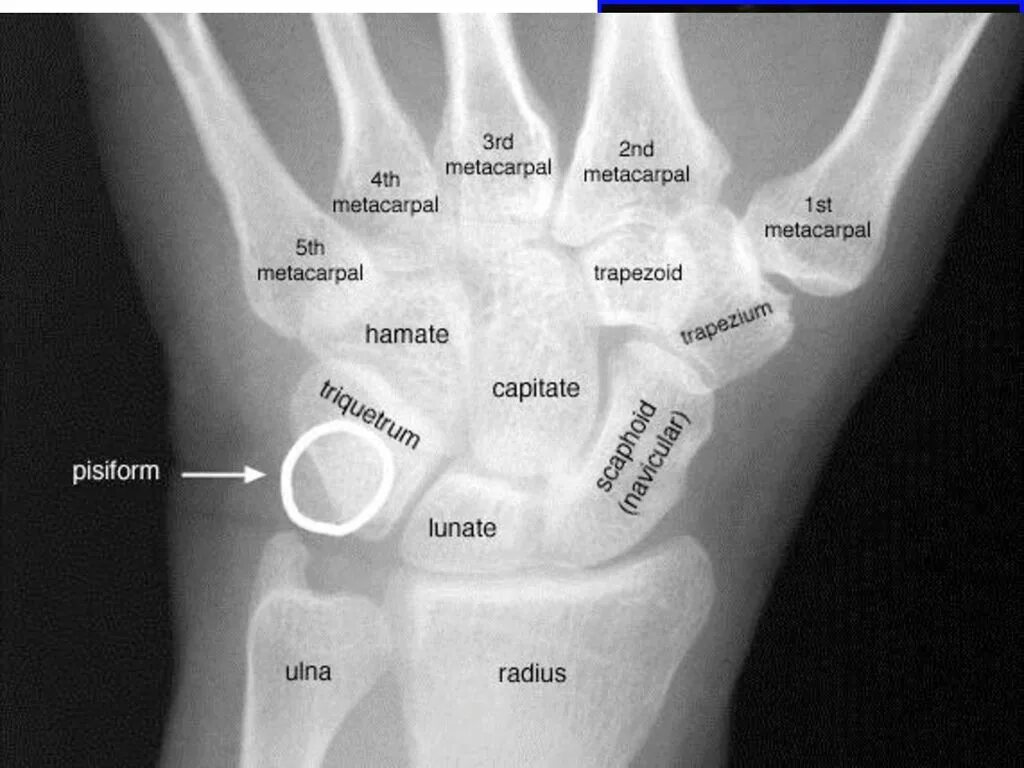

Снимок костей как называется